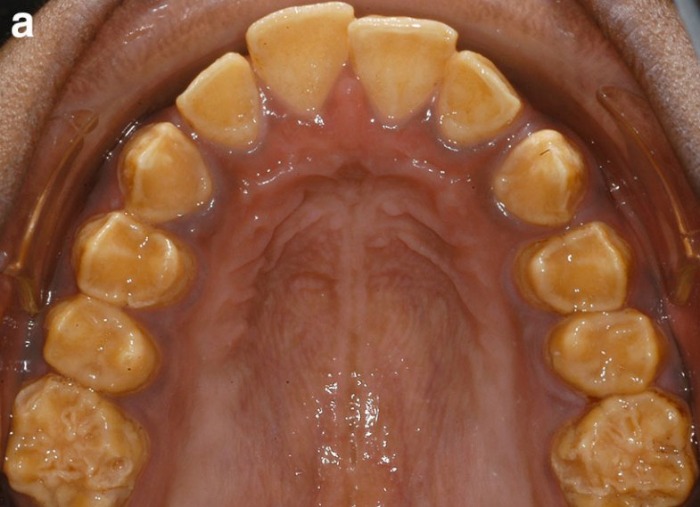

Клинические проявления AI заметно различаются в зависимости от типа AI; самые явно выраженные нарушения встречаются у гипопластического типа AI — вплоть до почти полного отсутствия эмали, не выявляемой ни клинически, ни рентгенографически. Однако чаще всего при гипопластическом AI эмаль тонкая, покрытая ямками, имеет желто-коричневый оттенок и высокую твердость. При гипоматурационном AI эмаль мягкая, опаковая, покрытая белыми, желтыми или коричневыми пятнами. При гипокальцифицированном AI наблюдается высокая истертость эмали, кроме того, она легко отделяется от подлежащего дентина. Дентин, затронутый AI, подвергается гистологическим изменениям вследствие утраты гипопластической эмали и становится гиперминерализированным; таким образом, морфологическая картина, наблюдаемая у дентина, пораженного AI, схожа со склеротизированным дентином (Sanchez-Quevedo et al, 2004).

о Гипопластический тип:

- Тонкий периферический слой рентгеноконтрастной эмали

- Открытые контакты: свободное пространство между зубами:

Зубы выглядят «подготовленными к протезированию коронок» (процедура подготовки к установке протеза, при которой удаляется часть коронки)

о Диффузный гладкий тип:

- Тонкий слой гладкой и твердой эмали на всех зубах

- Маленькие заостренные зубы с открытыми контактами

- Цвет зубов колеблется от матового белого до глянцевого коричневого